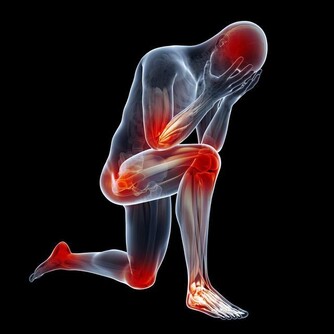

一、每天運動半小時,幫血管駐齡

堅持適度的體育鍛煉,不但可增加脂肪消耗,減少體內膽固醇沉積,降低血脂,加速血液循環,防止血液瘀滯,對於血管的健康很有好處。研究顯示,每天運動半小時,如騎自行車、游泳、乒乓球、慢跑、慢跑、散步、柔軟體操、打太極拳、爬樓或登山,都能起到減肥消脂的作用,提高血管“年輕化”程度,防止變老。